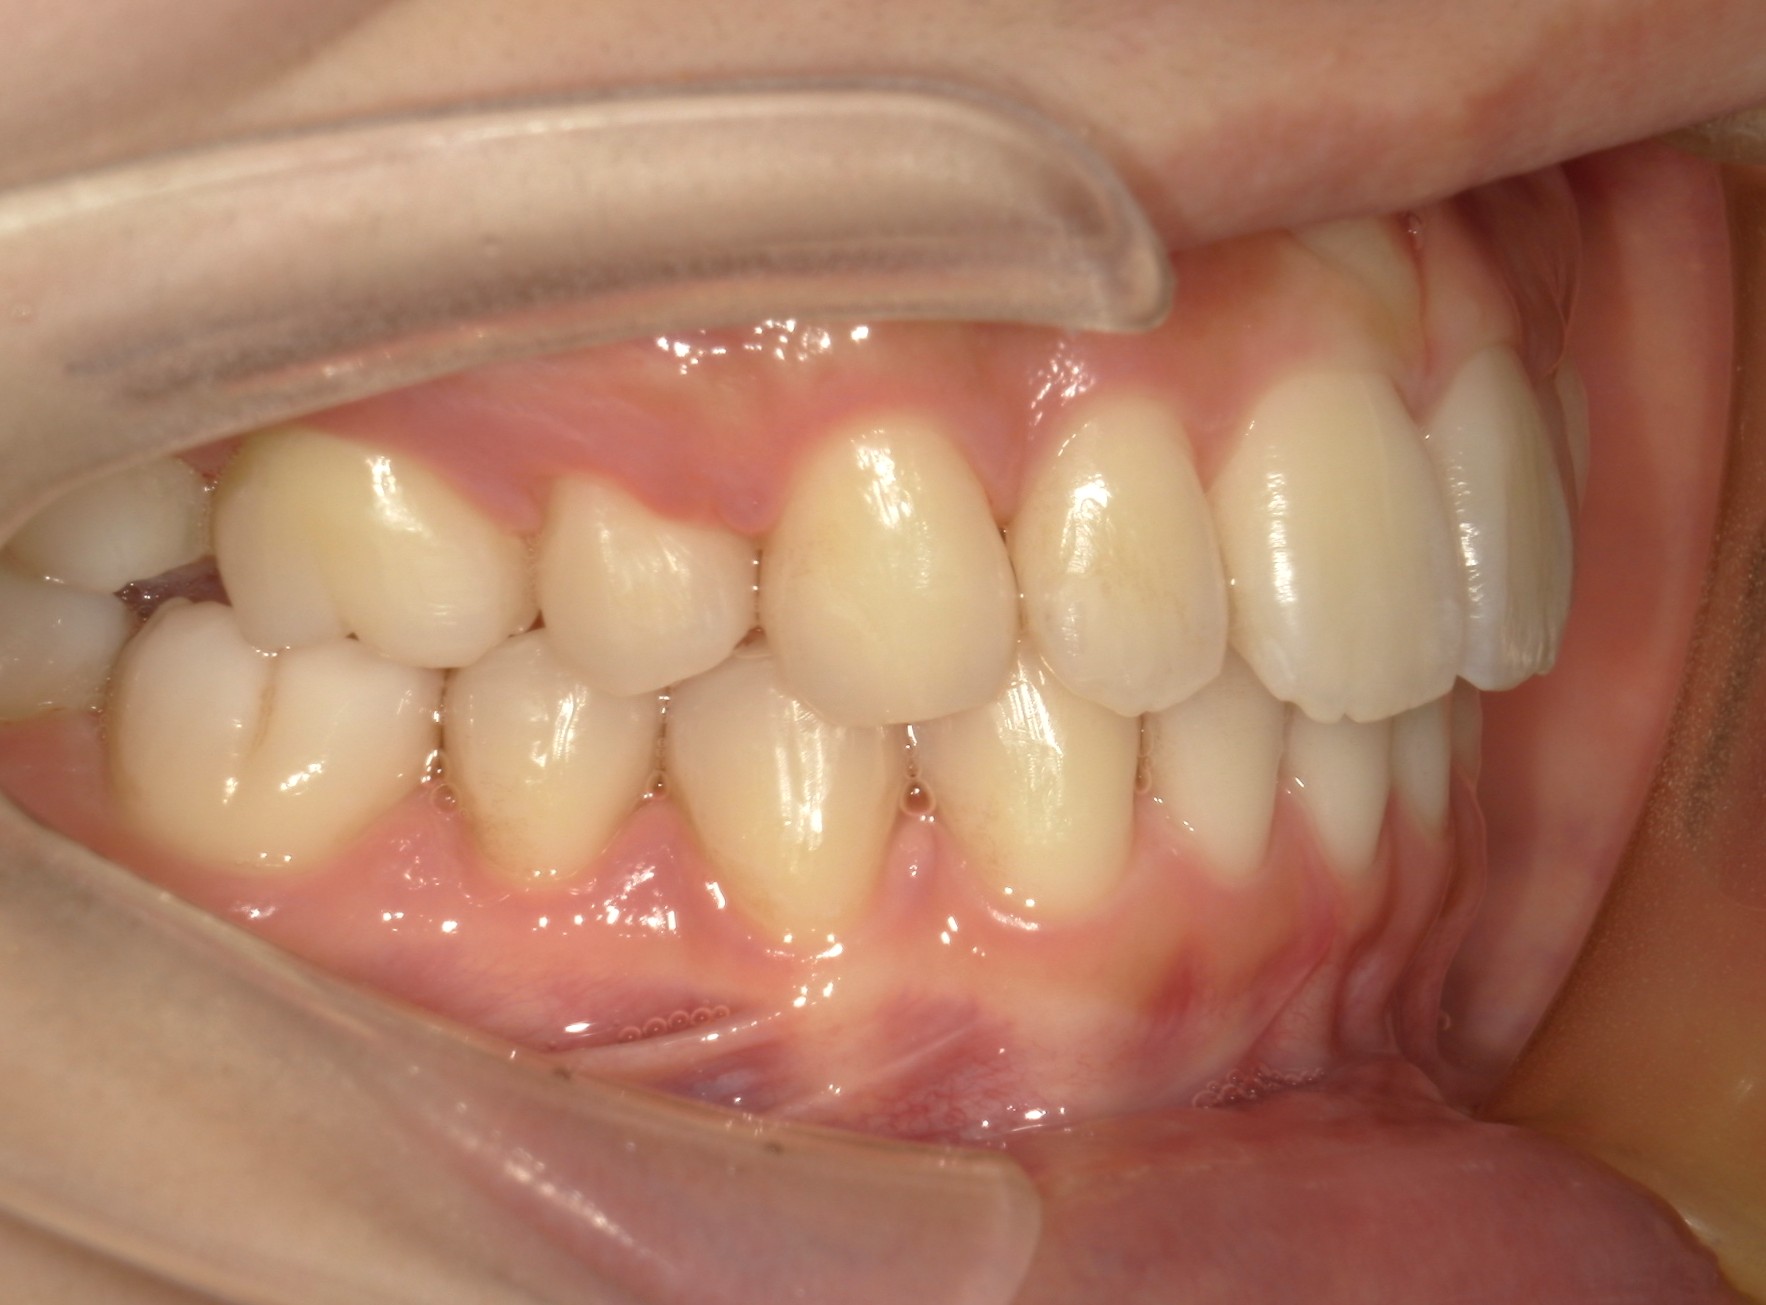

横から見た口腔内写真でよくわかるように、前歯が出っ歯になっており、全く咬んでいない状態でした。また下の前歯が本来4本あるところが、先天的に一本少なく3本しかない(Three incisors)であったため下顎のアーチが小さいというお口の状態でした。前歯を正しい傾きに治し、咬合させるため、上の歯のみ2本の抜歯を行うこととしました。下の前歯が3本のため、その正中に注意しながら前歯の傾きを修正し、奥歯のポジションを整えて仕上げました。口元の突出感は大きく改善し、咬合も良好な状態で完了することができました。

口内左

治療前

治療後